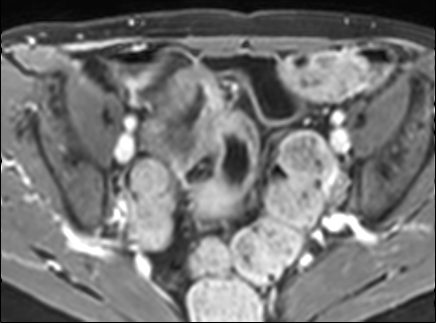

Bệnh nhân nữ 48 tuổi, đang điều trị bằng thuốc kháng TNF, được chỉ định nội soi đại tràng.

Phát hiện hẹp lòng ruột ở đại tràng sigma, không thể vượt qua được khi nội soi.

MR-enterography được thực hiện để đánh giá mức độ lan rộng của chỗ hẹp.

Cuộn qua các hình ảnh.

Ruột non bình thường, nhưng ghi nhận các đoạn hẹp ở đại tràng xuống và đại tràng ngang.

Cả hai đoạn hẹp đều có thành ruột dày đến 8 mm và ngấm thuốc rõ rệt theo kiểu niêm mạc ở đại tràng xuống và kiểu phân lớp ở đại tràng ngang.

Giãn ruột trước chỗ hẹp được ghi nhận ở cả hai đoạn.

Do các chỗ hẹp này không hiện diện khi nội soi đại tràng trước khi điều trị kháng TNF, nhiều khả năng chúng đã hình thành trong quá trình điều trị.

Do đó, quyết định phẫu thuật cắt đại tràng gần toàn bộ với miệng nối hồi-sigma đã được đưa ra.